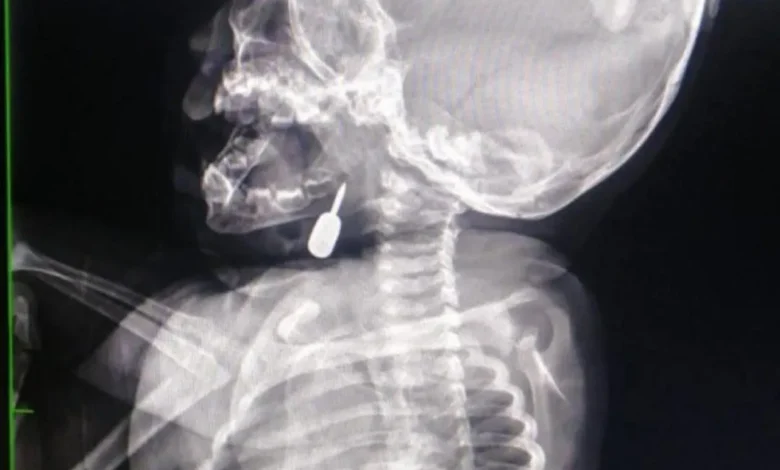

وفي تدخل طبي عاجل، أنقذ الدكتور السبول حياة طفل يبلغ من العمر أحد عشر شهراً، بعد أن وصل إلى قسم الطوارئ وهو يعاني من حالة اختناق حادة نتيجة وجود جسم معدني عالق في منطقة الحنجرة. وقد تم استخراج الجسم بنجاح، مما أسهم في إنقاذ حياة الطفل.